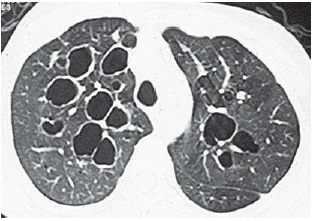

Observe a figura a seguir:

O diagnóstico é: